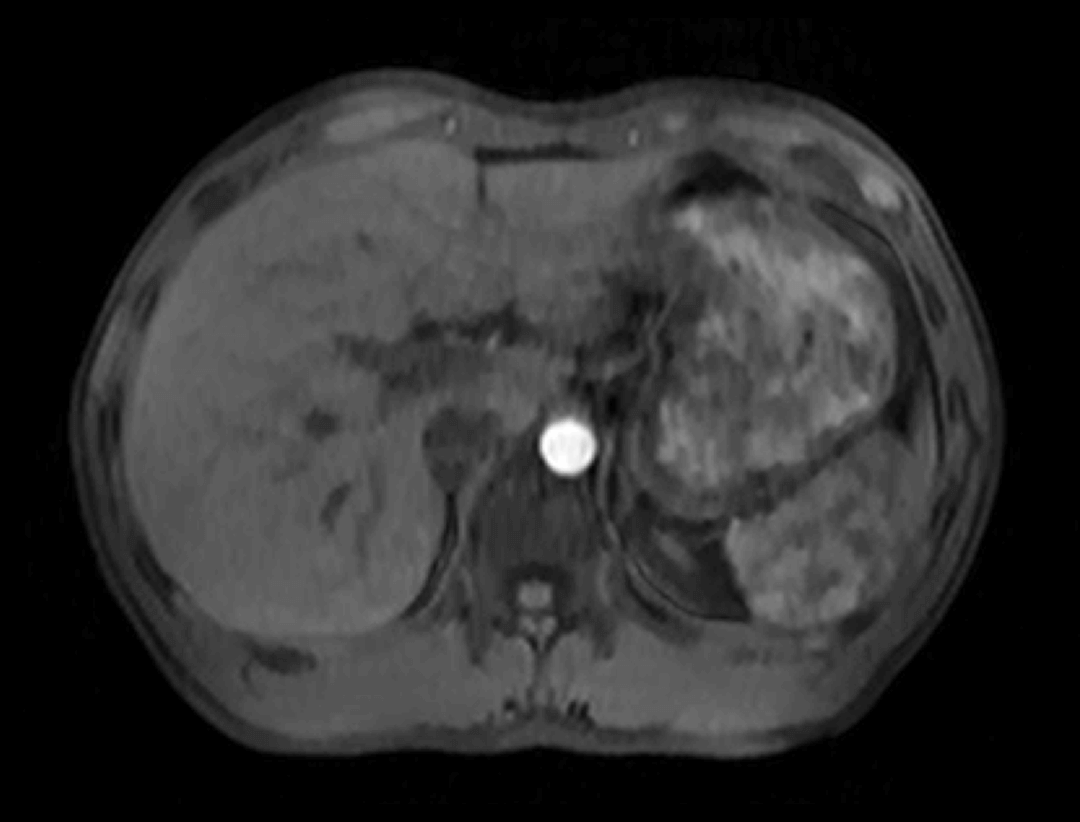

光梭®2.0成像应用

光梭®2.0成像应用于磁共振腹部动态增强扫描,可实现16倍采集加速,清晰捕捉组织信号连续动态变化,精准捕获腹部动态影像的每一瞬间,实时、全方位锁定病灶。